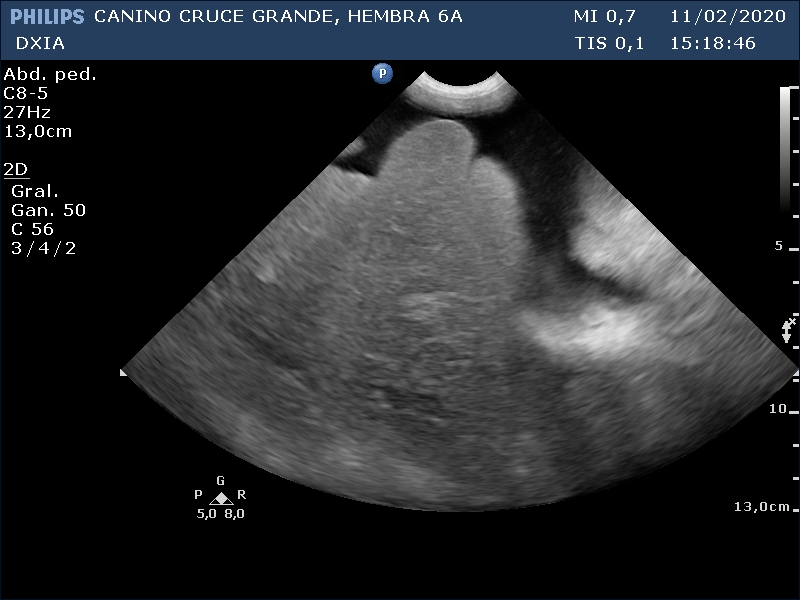

Durante el estudio ecográfico abdominal se observa:

- Marcada presencia de líquido libre abdominal con celularidad.

- Hepatomegalia con parénquima homogéneo.

Resto de órganos abdominales sin alteraciones significativas. Se comenta a la Veterinaria que se cree que la causa puede ser cardiaca, y tanto su Veterinaria como su propietario acceden a realizar estudio ecocardiográfico.

Se incluyen 3 imágenes del estudio:

Parénquima hepático homogéneo. Bordes hepáticos redondeados (Hepatomegalia). Presencia de líquido libre abdominal.